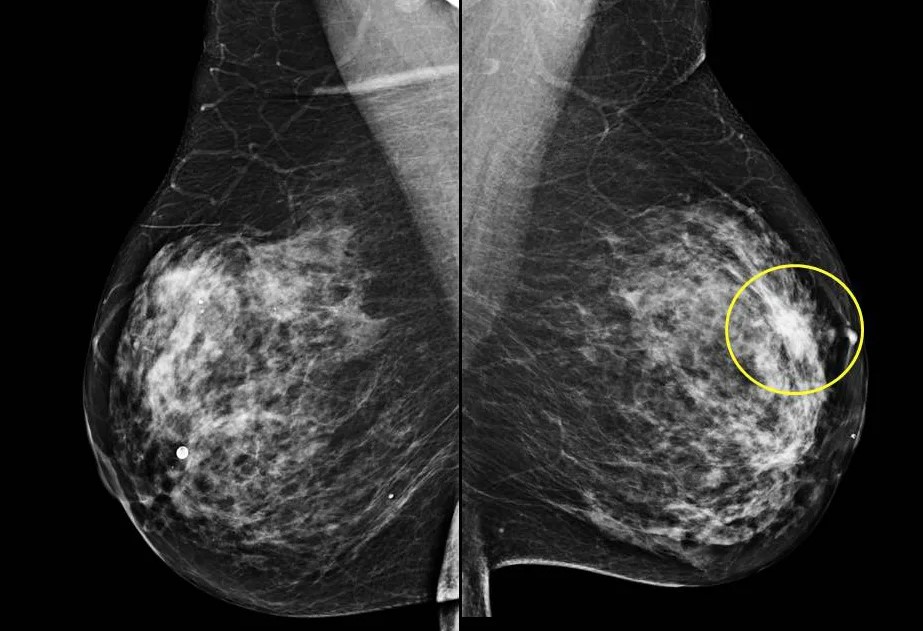

Важно четко понимать, что самообследование молочных желез и профессиональные методы диагностики не являются взаимозаменяемыми. Это два компонента единой стратегии по сохранению здоровья груди. Они не конкурируют, а дополняют друг друга. СМЖ позволяет отслеживать состояние груди на ежемесячной основе, в то время как клинический осмотр у врача, УЗИ и маммография являются более точными методами диагностики, способными выявить изменения, которые невозможно определить при пальпации.

Даже при регулярном и правильном выполнении самостоятельного осмотра необходимо придерживаться рекомендаций по плановым обследованиям: ежегодный осмотр у маммолога или гинеколога, УЗИ молочных желез (как правило, до 40 лет) и маммография (после 40 лет, с периодичностью, рекомендованной врачом). Только комплексный подход обеспечивает максимальную защиту и уверенность в здоровье молочных желез.